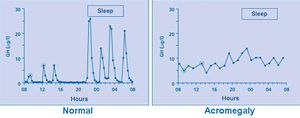

Frequent blood sampling with serum GH measurement shows that in normal subjects (left panel) GH can fluctuate between undetectable levels (most of the time) and peaks of up to 30 μg/l (90 mIU/l), owing to the episodic nature of GH secretion, while in patients with acromegaly (an example is given on right panel), GH hypersecretion is continuous and GH never returns to undetectable levels.